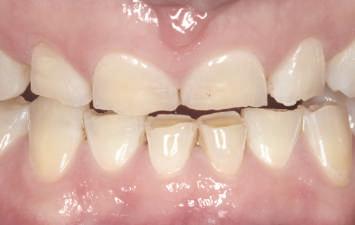

Dacă însă implanturile sunt plasate prea vestibular sau prea superficial, componentele nu permit un design adecvat al bontului, pentru că plasarea marginii este limitată iar conturul facial şi proximal poate fi compromis (fig. 1, 2).

Figurile 1, 2. Compromisurile conturului vestibular şi proximal sunt evidente. Implantul este la nivel tisular, tehnicianul neputând gestiona plasarea marginii sau a profilului intrasulcular pentru a îmbunătăţi estetica. Dacă se concepea un design tradiţional cu hexagon extern, marginea restauratoare s-ar fi putut plasa foarte aproape de interfaţa bont-implant, cu gestionarea mai bună a spaţiului.